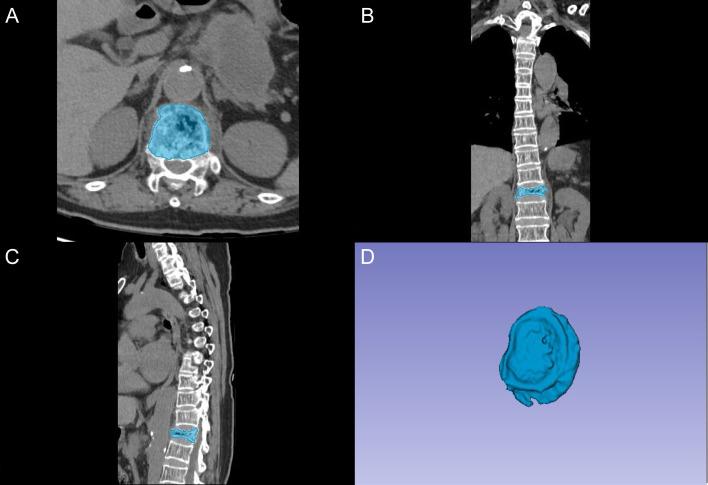

本前瞻性研究纳入了接受VA治疗OVCFs的患者。通过临床变量分析确定潜在预测因素。使用标准化椎体分割方案从术前CT图像中提取放射组学特征。研究人群按7:3的比例分为训练组和测试组。通过整合临床预测因素和放射组学特征构建了五个AI模型。在独立测试组中通过区分度、校准度和临床效用分析对模型性能进行评估。通过特征重要性分析解释最佳模型的预测机制。

在856名纳入患者中,102例(11.9%)出现了RBP。在所有评估算法中,TabNet表现出最佳性能指标(AUROC:0.927,召回率:0.833)。特征重要性分析显示椎体内真空裂隙和骨密度是主要临床预测因素,基于小波的纹理参数和定量强度指标起到补充作用。消融实验表明临床参数对减少假阳性至关重要,而放射组学特征增强了非RBP识别的特异性。该模型在不同阈值概率下保持一致的临床效用。通过深度学习框架整合临床参数和基于CT的放射组学能够准确术前预测RBP。